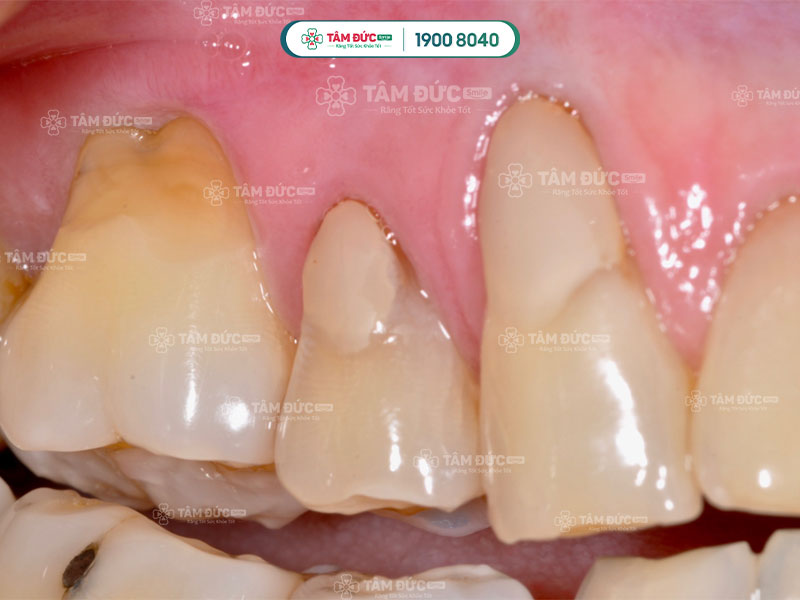

Tụt lợi hở chân răng còn được gọi là teo lợi. Đây là hiện tượng chân răng bị lộ ra do mô nướu co lại hoặc di chuyển mạnh mẽ.

Ở giai đoạn đầu, tụt lợi hở chân răng phát triển một cách âm thầm nên rất khó nhận biết. Quý khách chỉ nhận ra khi mô nướu đã bị teo và phần chân răng lộ nhiều hơn. Lúc này, Quý khách có thể cảm thấy ê buốt, đau nhức và dễ bị chảy máu chân răng.

Khi mô nướu bị tụt sâu, đặc biệt là ở răng cửa, chân răng bị để lộ nhiều làm răng trông có vẻ dài hơn. Điều này rất ảnh hưởng đến thẩm mỹ nụ cười và làm Quý khách thiếu tự tin khi giao tiếp.

3.2. Răng nhạy cảm và ê buốt

Phần chân răng không được men răng bảo vệ như phần thân răng. Lợi bị tụt xuống làm hở chân răng, phơi ra lớp ngà răng làm cho răng trở nên nhạy cảm. Đó là lý do vì sao Quý khách thường cảm thấy ê buốt trong mỗi bữa ăn hoặc khi để răng tiếp xúc với không khí.